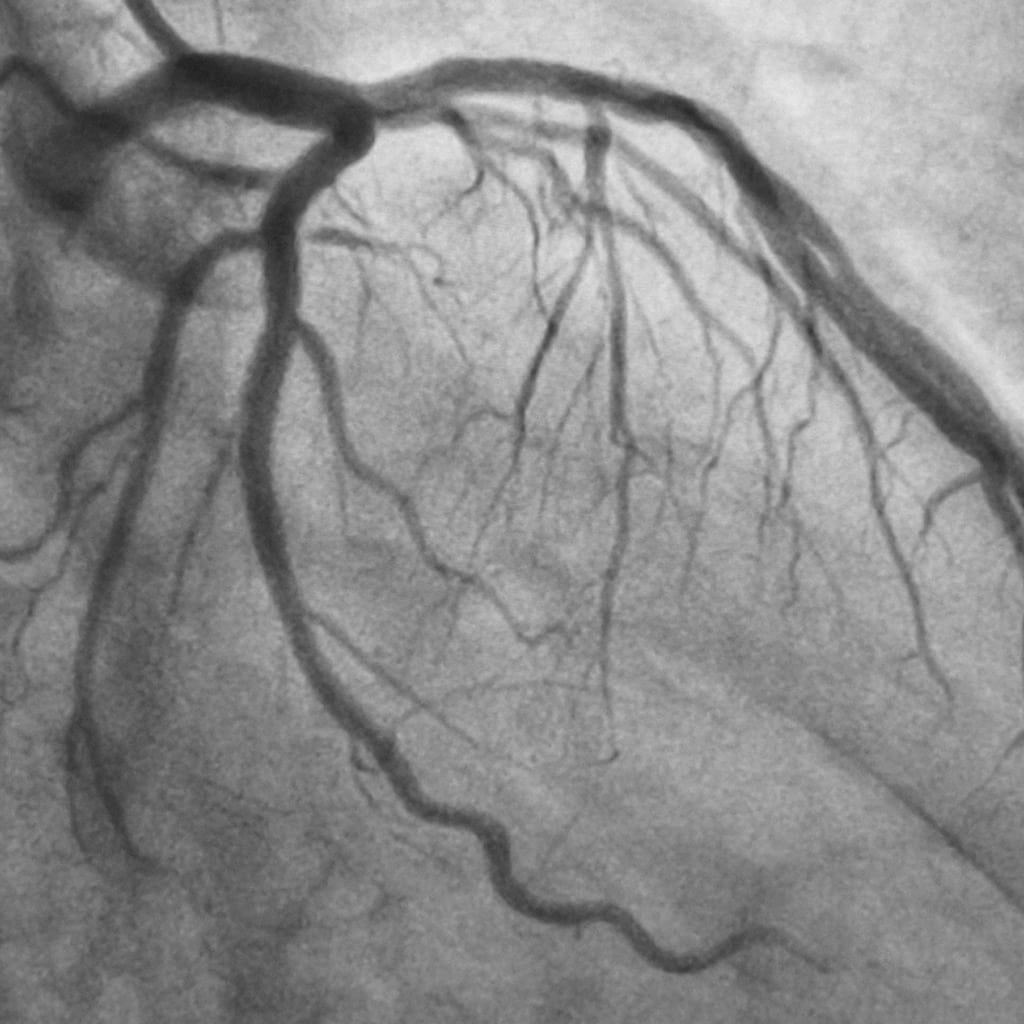

Percutaneous Transluminal Coronary Angioplasty, also called PTCA, includes utilizing a catheter with an inflatable-like gadget to broaden the limited conduit and restore blood flow to the heart. This procedure is performed by skilled cardiologists who have some expertise in PTCA and work intimately with a group of healthcare experts to guarantee ideal results for patients. With regards to Coronary Angioplasty (PTCA) procedures, considering an accomplished and skilled Coronary Angioplasty (PTCA) doctor is significant for exact diagnoses and powerful treatment.

The Procedure: During the PTCA procedure, the cardiologist embeds a flimsy, adaptable catheter through a little cut, typically in the crotch or arm, and guides it to the obstructed coronary course. The catheter is outfitted with an emptied swell-like gadget, which is then expanded to push the plaque against the course walls, enlarging the supply route and restoring blood flow. At times, a stent (a little mesh tube) might be embedded to assist with keeping the course open.